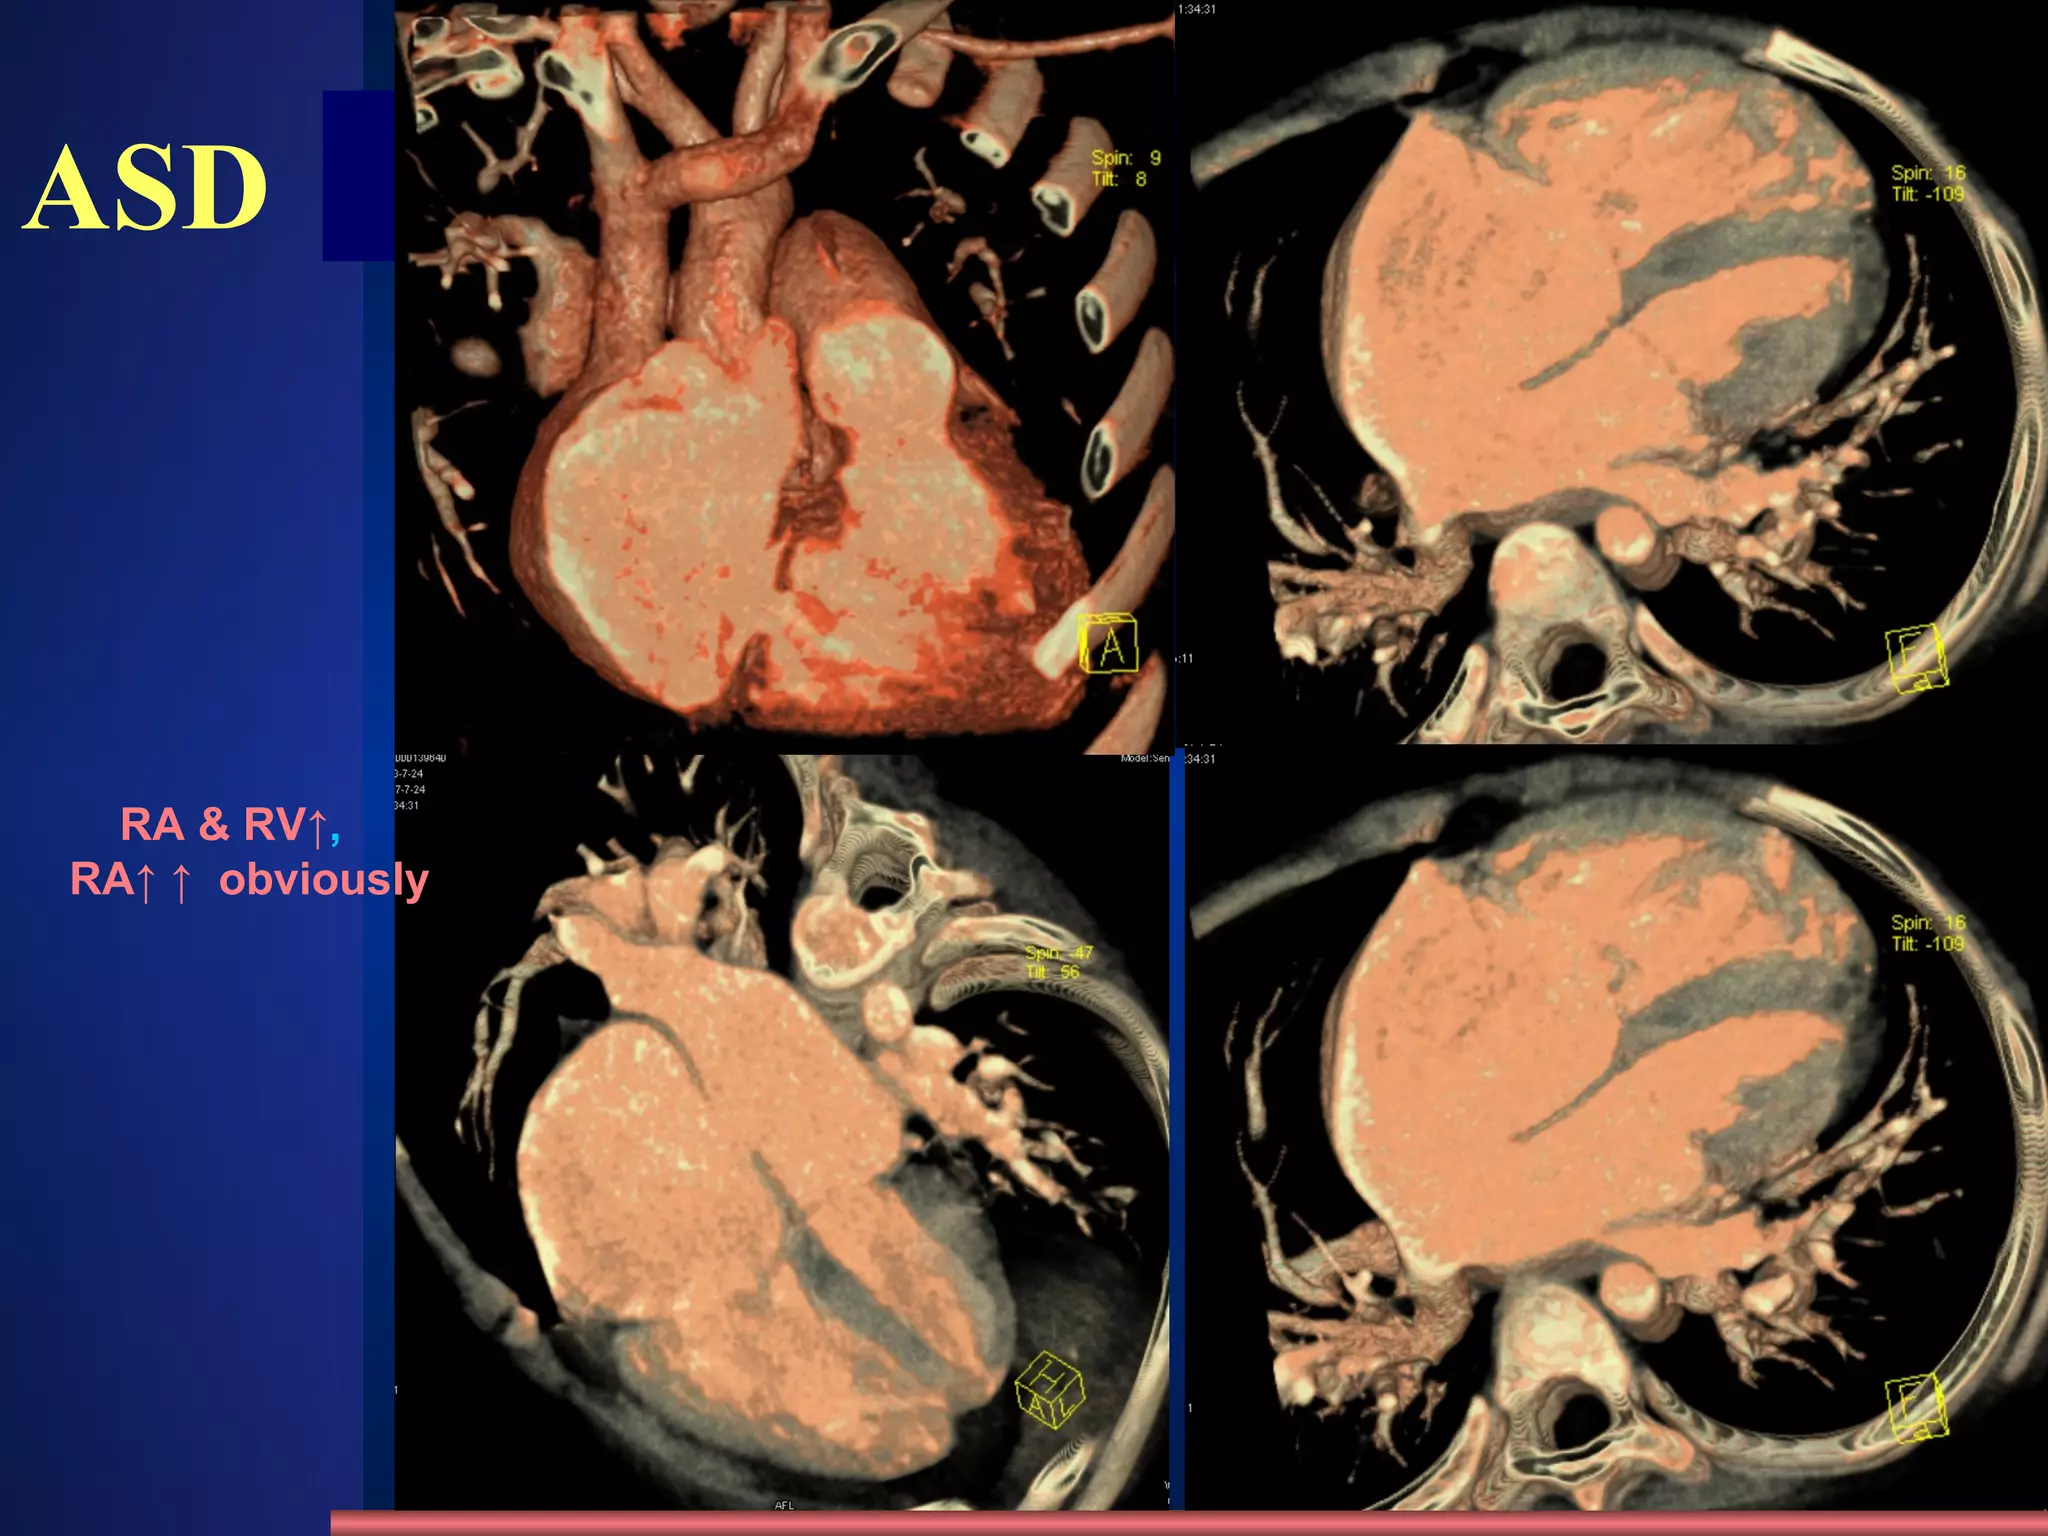

ASD Clinic mostly adult  SM on the 2th-3rd intercostal of the left sternal border Change of hemodynamics X-ray appearance Cardiomegaly , “mitral configuration” RA & RV↑ ,  RA↑ ↑   obviously Pulmonary artery segment bulge  , hilum angiectasia, hilum dance pulmonary blood flow↑ ↑. PAH in later stage LA do not enlarge, LV and aorta shrink /231 4 type: Ostium primum , ostium secundum Sinus venosus , coronary sinus Fossa Ovalis defect 80~90% Atrial septal defect methods normal abnormities diseases

ASD aorta shrink RA & RV↑ ,  RA↑ ↑   obviously RA RV PA Aorta svc

ASD RA & RV↑ ,  RA↑ ↑   obviously

ASD /231 Enlargement of RA methods normal abnormities diseases RA RV PA Aorta svc